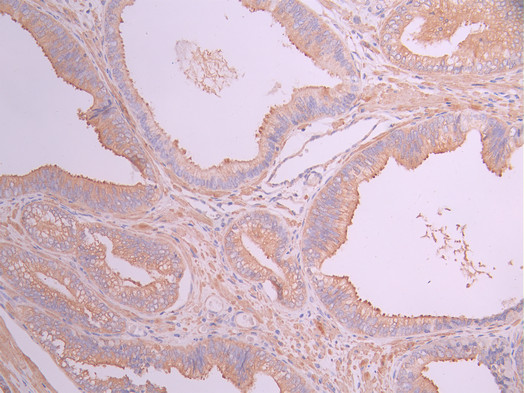

• IHC image of CSB-RA184907A0HU diluted at 1:100 and staining in paraffin-embedded human prostate cancer performed on a Leica BondTM system. After dewaxing and hydration, antigen retrieval was mediated by high pressure in a citrate buffer (pH 6.0). Section was blocked with 10% normal goat serum 30min at RT. Then primary antibody (1% BSA) was incubated at 4°C overnight. The primary is detected by a Goat anti-rabbit polymer IgG labeled by HRP and visualized using 0.05% DAB.